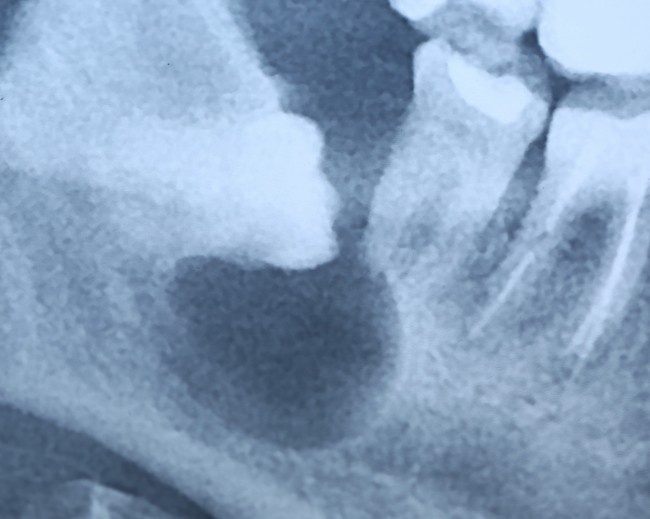

И что мы видим? Под зубом образовалась гигантских размеров фолликулярная киста. То есть, теперь нам нужно не только удалять ретинированный зуб мудрости, но и фолликулярную кисту. А для этого, кстати, придется депульпировать соседний седьмой зуб:

И хорошо, что это, всего лишь восьмерка — удалили зуб, удалили кисту и забыли о проблеме. Но ретинированный зуб, как и сверхкомплектный, может быть любым и в любом месте. И в случае, если он находится в пределах зубного ряда, нам нужно не только удалять его и образованную им кисту, но и думать о судьбе соседних зубов. Вот пример — гигантская фолликулярная киста, которая привела к потере всех нижних передних резцов: